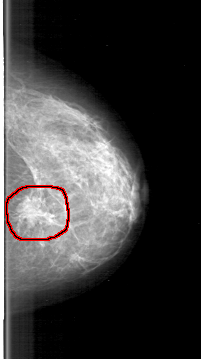

D_4106_1.LEFT_MLO

LEFT_MLO LINES 5341 PIXELS_PER_LINE 2656 BITS_PER_PIXEL 12 RESOLUTION 43.5 OVERLAY

FILE: D_4106_1.LEFT_MLO.OVERLAY

TOTAL_ABNORMALITIES 1

ABNORMALITY 1

LESION_TYPE MASS SHAPE IRREGULAR MARGINS SPICULATED

ASSESSMENT 5

SUBTLETY 4

PATHOLOGY MALIGNANT

TOTAL_OUTLINES 1

BOUNDARY